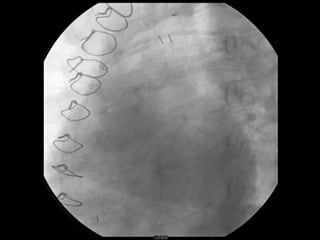

MATERIAL RETIRADO DO FILTRO

RETIRADA DO FILTRODE PROTEÇÃO